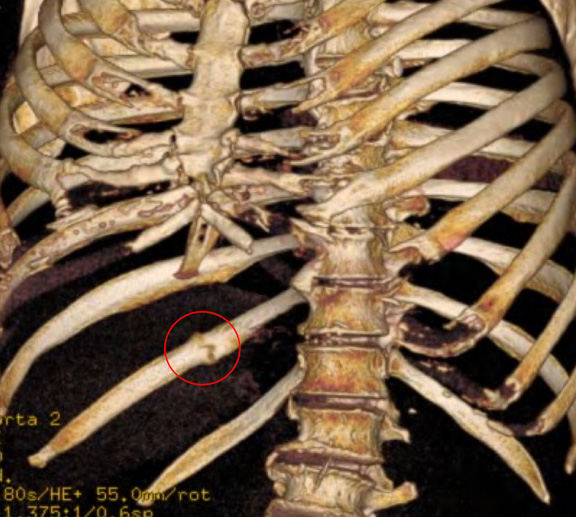

Open reduction and internal Rib fixation following a right chest wall injury and 4 rib fractures following fall downstairs (red ring).

CT reconstruction chest in a patient with persistent and long-standing chest wall pain and tenderness at the site of an old poorly healed right 11th rib fracture (red ring). The painful area was excised and the pain resolved.